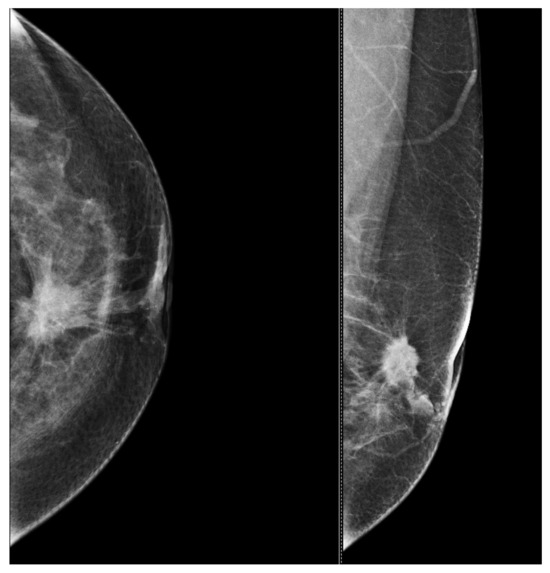

6.1. Characterization of Lesions

9. Types of Lesions Found by Screening with Breast Ultrasound